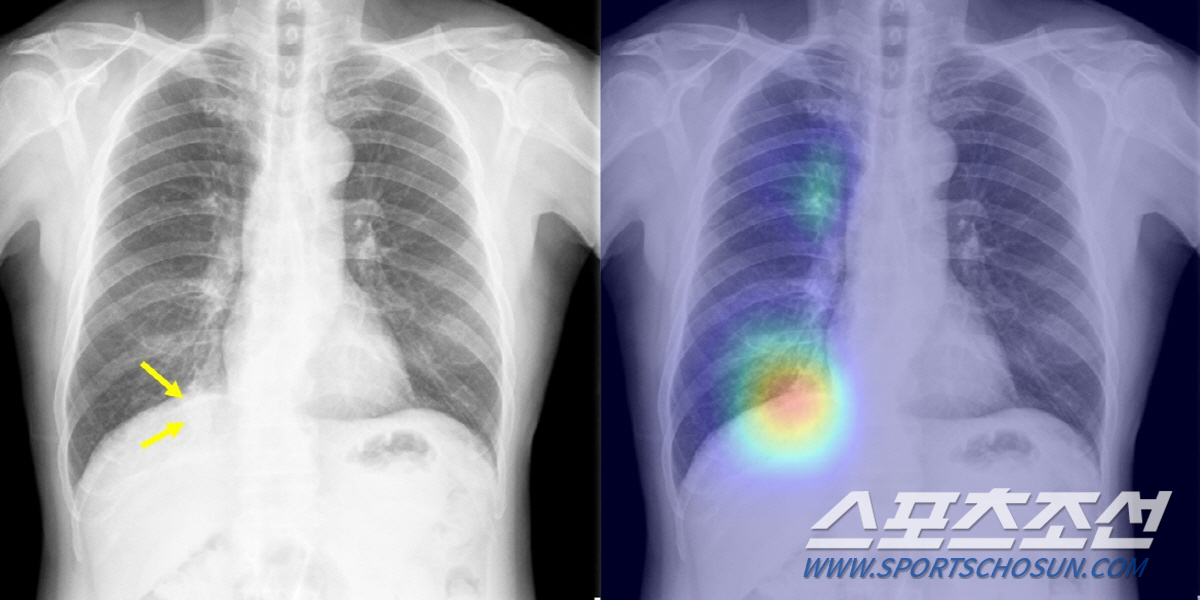

응급실에서 촬영된 흉부X선 영상을 판독한 결과, 당직 영상의학과 의사의 판독민감도(sensitivity)는 66%에 머물렀으며 촬영된 영상을 판독하는데 88분(중앙값)이 소요됐다. 특히 추가검사나 치료가 필요한 이상소견이 있는 영상은 114분(중앙값)이 걸렸다. 영상 판독결과를 기다리는데만 약 1~2시간이 지체되는 셈이다.

반면 인공지능 진단시스템으로 판독했을 때 판독 민감도는 82~89%로 당직의사보다 높았다. 또한, 당직의사가 인공지능 진단시스템 분석결과를 참고해 진단했을 때도 판독 민감도가 향상됐다. 이처럼 응급실에서 인공지능 진단시스템을 활용한다면, 판독오류와 소요시간을 줄임으로써 진료지연을 개선할 수 있을 것으로 기대된다.